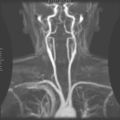

الشريان السباتي الظاهري، هو أحد الشرايين الرئيسية في الرأس والعنق. يتفرع الشريان السباتي الأصلي إلى الشريان السباتي الظاهري والغائر. يمد الشريان السباتي الظاهري الدم للوجه والعنق.[1]

يبدأ الشريان السباتي الظاهر عند الحد العلوى للغضروف الدرقي وينحنى ماراً إلى الأمام وإلى الأعلى ثم يميل للخلف في الفراغ خلف رقبة الفك حيث ينقسم إلى الشريان الصدغي والشريان الفكي داخل الغدة الدرقية.

ينقسم الشريان السباتي الظاهر إلى الفروع الرئيسية التالية، ووظيفتها جميعاً تزويد الوجه وأجزاؤه والأجزاء خارج الجمجمة من الرأس، والرقبة بالدم: